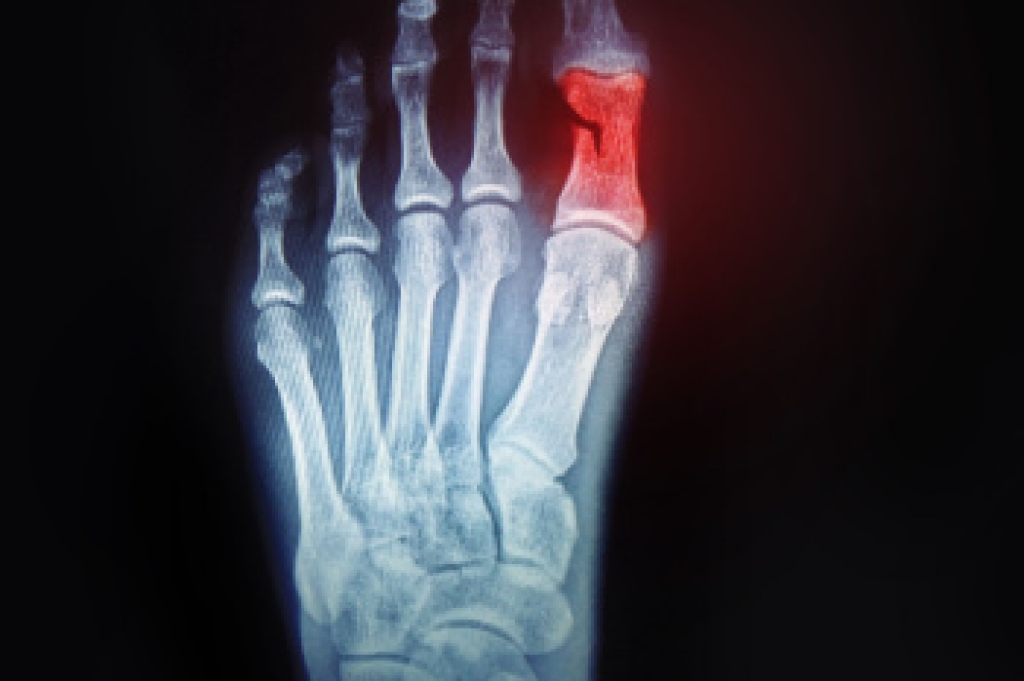

Your feet are a critical part of your overall health, and our podiatry services focus on diagnosing and treating disorders of the lower extremity to ensure your feet remain healthy and functional. We provide diabetic foot care and treat a range of issues, including foot and heel pain, bunions, hammertoes, fungal nails, plantar fasciitis, ingrown toenails, ankle pains, varicose veins, and leg swelling. We use advanced surgical techniques to correct foot problems and minimize scarring, specializing in bunion and hammertoe surgery, as well as Achilles' tendon repair.